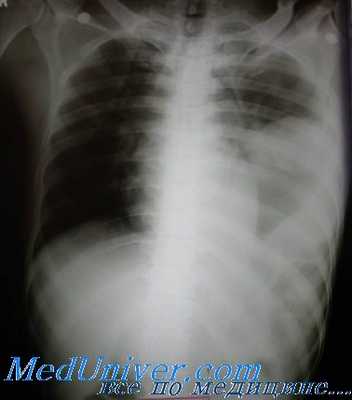

Рисунок 1. Анатомия диафрагмы и ее крупных отверстий Рисунок 2. А, Б. Грыжа левой половины диафрагмы после колотого ранения левой торакоабдоминальной области много лет назад: в левой части грудной клетки видны желудок и ободочная кишка Рисунок 3. А. Проникающее ранение левой половины диафрагмы (кружок). Рваная рана при проникающей травме довольно небольшая, обычно около 3—4 см в длину. Б. Разрыв левой половины диафрагмы в результате тупой травмы (стрелки). Разрыв при тупой травме крупный, обычно около 7—8 см в длину. Травмы, обусловленные замедлением, могут вызвать отрыв диафрагмы от мест ее прикрепления Рисунок 4. Все бессимптомные проникающие ранения левой торакоабдоминальной области между соском и нижним краем реберной дуги требуют проведения лапароскопии, чтобы исключить повреждение диафрагмы

• При проникающих ранениях размер разрыва диафрагмы составляет около 3—4 см. При тупой травме он значительно больше — примерно 7—8 см (рис. 3, А, Б).

• При любом бессимптомном проникающем ранении левой торакоабдоминальной области между соском и нижним краем реберной дуги необходимо проведение лапароскопии, чтобы исключить повреждение диафрагмы (рис. 4). Отсутствие отклонений по результатам рентгенографии органов грудной клетки или КТ не позволяет достоверно исключить повреждение диафрагмы.